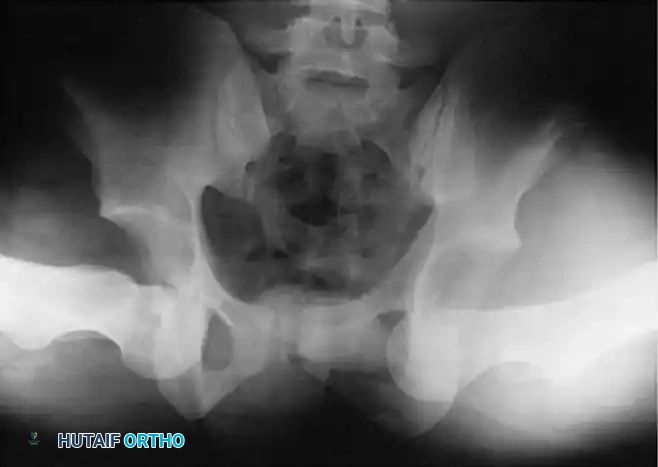

Fig. 57-9 Bilateral obturator dislocations of the hip. Note the profound abduction and inferior displacement of the femoral heads.